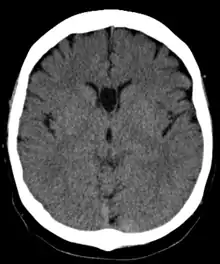

The cave of septum pellucidum (CSP), cavum septi pellucidi, or cavity of septum pellucidum is a slit-like space in the septum pellucidum that is present in fetuses but usually fuses during infancy. The septum pellucidum is a thin, laminated translucent vertical membrane in the midline of the brain separating the anterior horns of the right and left ventricles. It lies posterior to the corpus callosum. Persistence of the cave of septum pellucidum after infancy has been loosely associated with neural maldevelopment and several mental disorders that correlate with decreased brain tissue.[1][2][3][4][5]

The cave of septum pellucidum is bounded anteriorly by the genu of the corpus callosum, superiorly by the body of the corpus callosum, posteriorly by the anterior limb and pillars of the fornix, inferiorly by the anterior commissure and the rostrum of the corpus callosum, and laterally by the leaflets of the septum pellucidum.[6]

In prenatal development of the fetus, the laminae of the septum pellucidum separate to form a small cavity – the cave of septum pellucidum. This is an important normal structure to identify in the sonographic assessment of the fetal brain. In post-natal life, the laminae of the septum pellucidum usually fuse, which obliterates the cavum. The cavity contains cerebrospinal fluid (CSF) that filters from the ventricles through the septal laminae.[7]

There are individual differences in the degree of CSP; whereas some have complete closure of the cavum, others present with a small degree (4–6 mm wide, in the coronal plane) of incomplete closure.[4] The most common type of CSP is noncommunicating; that is, it does not connect to the brain's ventricular system. Because of this lack of communication, the previous use of the term "fifth ventricle" is no longer used, and the fifth ventricle is the name often used for the terminal ventricle.